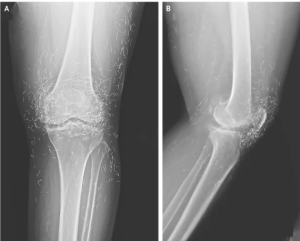

A routine X-ray revealed a shocking discovery: hundreds of tiny gold needles embedded in the knees of a 65-year-old woman suffering from severe osteoarthritis.

The woman had turned to acupuncture after standard treatments, including painkillers and anti-inflammatory medications, failed to ease her joint pain.

Acupuncture, a traditional therapy widely used in Asia, sometimes involves leaving thin metal needles in tissue to provide continuous stimulation, though this practice carries risks.

Experts warn that foreign objects in the body can trigger inflammation, infection, or abscesses, and metal fragments can interfere with imaging or become dangerous during an MRI.

While gold-thread acupuncture remains common in some Asian countries and has gained limited popularity in the U.S., scientific evidence supporting its long-term benefits is scarce. Patients should carefully weigh potential advantages against serious complications before pursuing such extreme alternative treatments.

The South Korean woman’s case, recently documented in the New England Journal of Medicine, serves as a cautionary example. What may seem like a harmless alternative therapy can carry hidden dangers, highlighting the importance of consulting medical professionals and understanding risks before undergoing unconventional procedures.